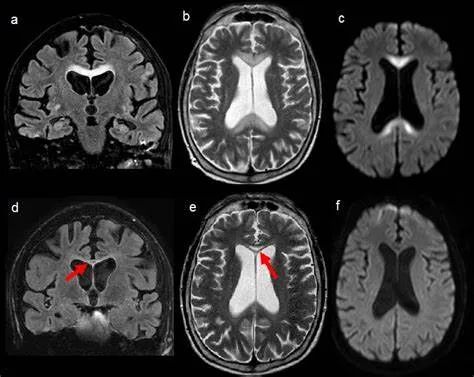

•随着病变进展至亚急性期和慢性期,胼胝体内可出现坏死、囊变,以膝部及压部表现为著。在膝部和体部常表现为中心夹层状异常信号,类似“三明治”状,其境界清楚,据认为这是本病的特点之一。病理检查证实,病变主要对称性侵及胼胝体的中心层,而背、腹层面的组织结构相对完好。主要的组织学所见为脱髓鞘,少突胶质细胞明显减少,而含脂巨细胞大量增多。部分病例在T2加权像上,偶见胼胝体变性、坏死区内出现极低信号,镜下病理显示含脂巨细胞内可见散在或成堆的含铁血黄素分布,可能为T2异常低信号的病理基础。

上排:原发性胼胝体变性急性期

下排:原发性胼胝体变性慢性期,表现为胼胝体萎缩、软化

急性期原发性胼胝体变性(胼胝体压部及体部病变,CT呈低密度,T1WI呈稍低信号,FLAIR呈稍高信号,扩散受限)向慢性期转变,慢性期胼胝体压部病灶出现坏死或囊变,FLAIR呈低信号